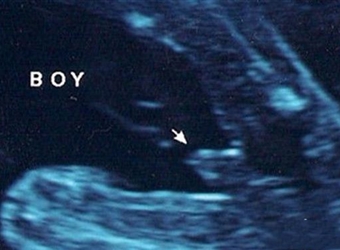

现在有许多妈妈说通过四维彩超可以查看男女,说是四维彩超里男女宝宝图片是有区别的,为了证实这一切的真假性,下面,赶紧随本文一起来看看,四维男女宝宝区别…

有人说四维彩超单上的F和M字母代表胎儿性别,m开头是男孩f是女孩对,难道四维单子有暗示男女吗?如果真的如传言所说,那么问题又来了,四维单子上怎么看m和f呢?